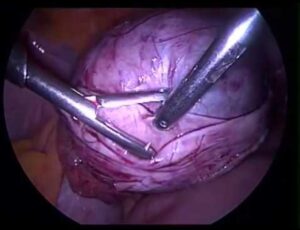

تنظير البطن هي تقنية جراحية التي تدخل تحت مجموعة التقنيات الجراحية محدودة الاختراق للجسم (باضعة بشكل صغير) أو المنظار. والمقصود هو الجراحات التي تهدف للتشخيص أو العلاج بواسطة الاستعانة بجهاز تلسكوبي دقيق الذي يتم إدخاله إلى الجسم من أجل فحص التجويفات الداخلية. وما يميز هذا العلاج هو أنه يمكننا من التشخيص والعلاج الجراحي للكثير من الأمراض التي تصيب أعضاء البطن والحوض دون الحاجة للقيام بشق جراحي.

تقنية الجراحة بواسطة التنظير البطني تعتمد على عدة مراحل ثابتة، والتي تشمل: استلقاء المريض والقيام بتخديره بشكل تام، إدخال إبرة خاصة من خلال جدار البطن وضخ غاز ثاني أكسيد الكربون من خلالها من أجل نفخ تجويف البطن، ثم يتم إدخال منظار البطن لداخل تجويف البطن بواسطة كم خاص بقطر 1 سم يتم إدخاله عادة عبر السرة، يتم تفحص البطن والحوض بواسطة الصورة التي تنتقل عن طريق منظار البطن إلى الشاشة، ثم يتم إدخال أدوات الجراحة عبر 2-3 شقوق صغيرة جدا في البطن، والقيام بالعملية المخطط لها.